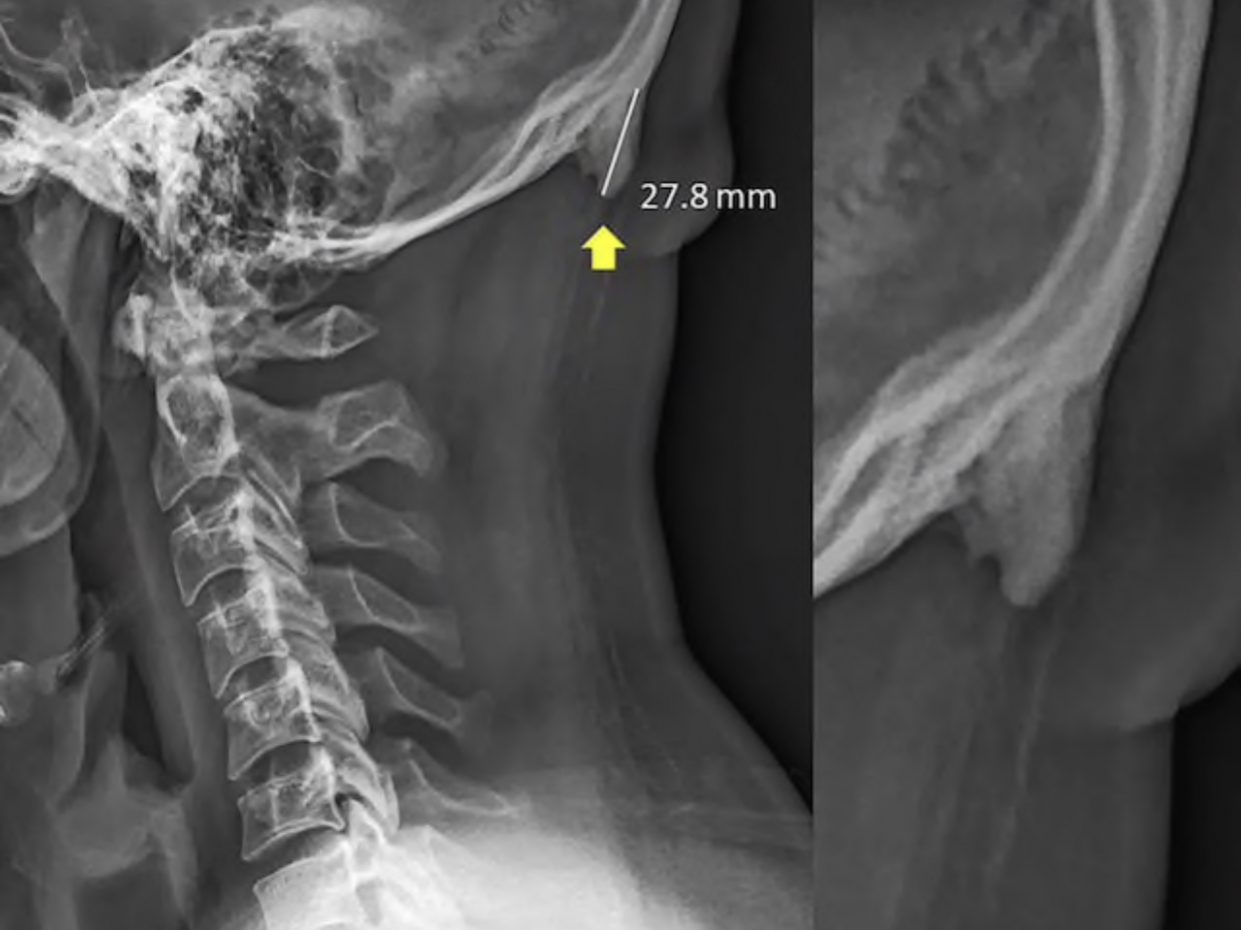

Да-да. Прямо на затылке развиваются рогообразные выступы из-за постоянно опущенной головы. Это приводит к смещению нагрузки от позвоночника к мышцам головы, отчего растут кости в сухожилиях и связках.

Зачастую такие отростки образуются у людей в возрасте от 18 до 30 лет.